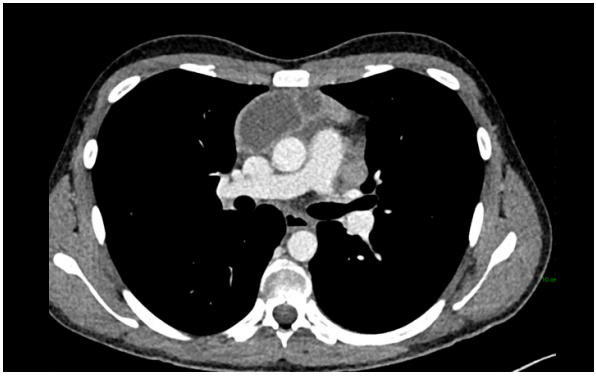

Step 1

The patient underwent a CT scan the following day. A multilocular cystic mass was identified on CT in the mediastinum, accompanied by numerous enlarged lymph nodes located centrally in the chest.